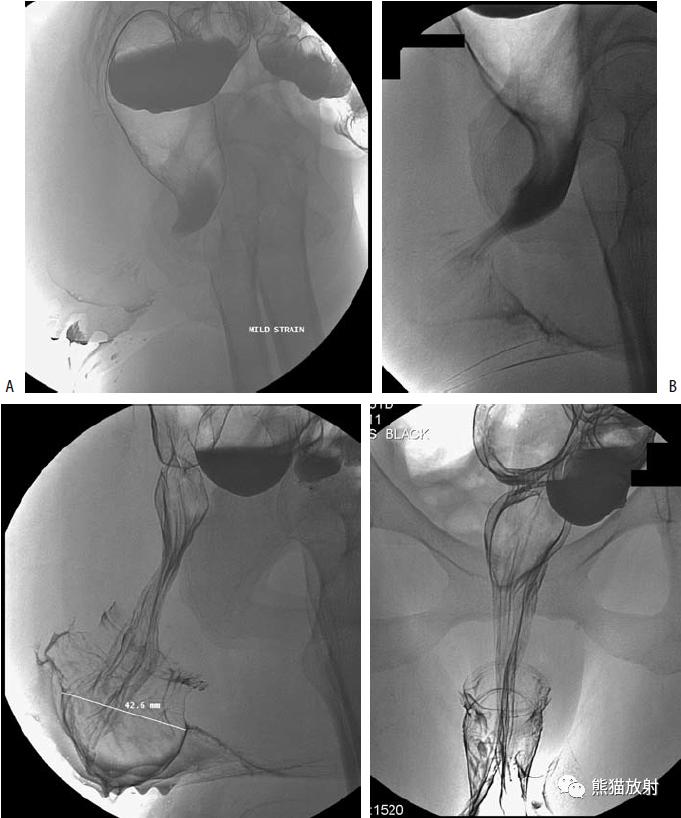

回-结肠套叠。CT定位像示7岁患儿的肠套叠(箭头)。Burkitt淋巴瘤所致。右图:10个月大的婴儿,疼痛和右上腹肿块。X线平片示横结肠(箭头)区域有软组织肿块。钡灌肠证实为肠套叠。

巨大的乙状结肠憩室。X线平片示盆腔巨大充气结构(箭头)。钡灌肠确定为憩室(箭头),并与结肠相连。